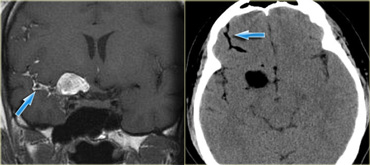

Ruptured dermoid cyst. Coronal T1WI (left) and NECT (right). Ruptured dermoid cyst. Coronal T1WI (left) and NECT (right).

On the left a patient with the classical findings of a ruptured dermoid cyst.

Some tumors can have a high density on CT.

This is typically seen in lymphoma, colloid cyst and PNET-MB (medulloblastoma).